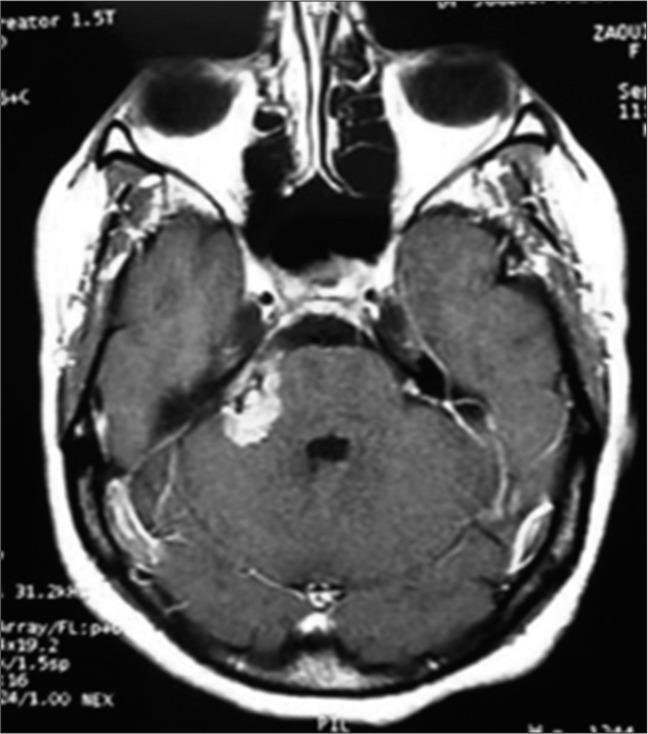

We report the case of a 50-year-old woman who presented with a large right full cystic VS revealed by a balance disorder associated with deafness in the right ear which spontaneously regressed. The patient was lost to follow-up for 3 years, the symptomatology improved, and the tumor clearly regressed without any surgical treatment.

Spontaneous regression of solid-cystic VS is possible but rare, it can be part of conservative treatment, which requires regular follow-up.